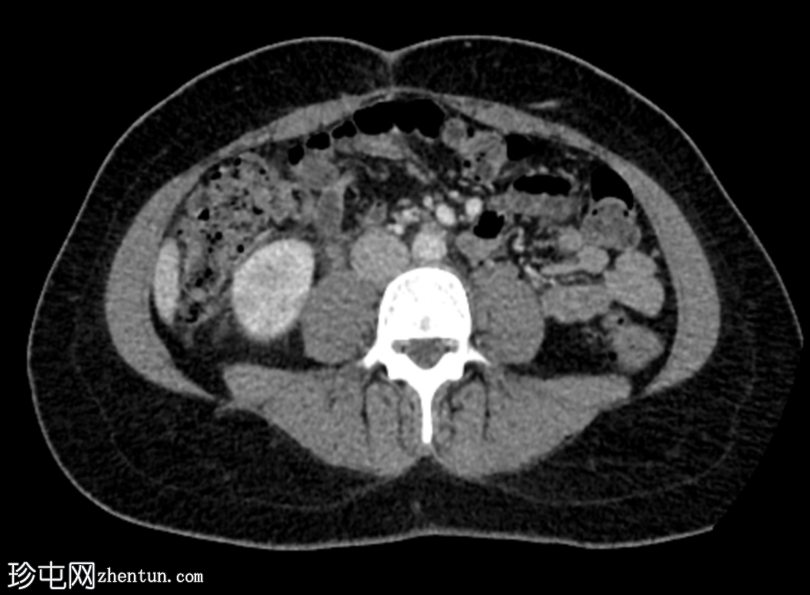

轴位增强扫描(门静脉期)

右肾在轴位和冠状位图像上均可见多个楔形低强化区,伴有轻度肾周脂肪间隙模糊。

双侧肾盂及输尿管轻度壁增厚和强化。

膀胱壁轻度增厚。

影像

学表现提示右侧急性肾盂肾炎和左侧肾盂及输尿管炎。